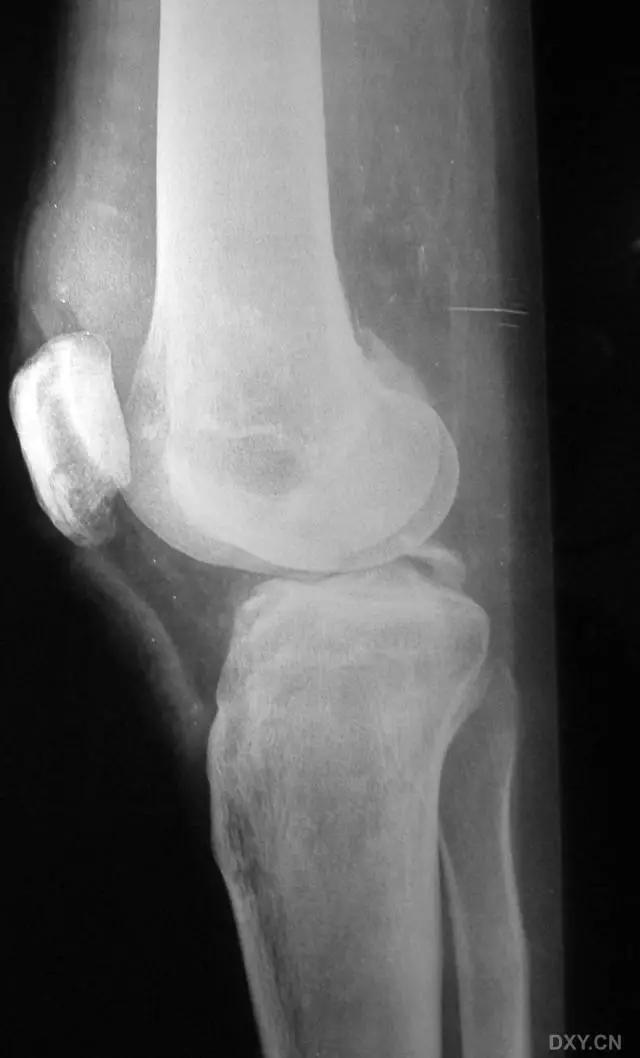

8. Segond 骨折和反向 Segond 骨折

(1)Segond 骨折

是发生在胫骨平台外侧的垂直撕脱性骨折。这种骨折在前后位 X 线片上显示最佳。屈曲位时膝关节受到内旋*力暴**作用,导致皮质骨撕脱性骨折,这种骨折常发生在运动员身上。

常引起股骨内髁和胫骨平台后内侧骨挫伤,75%~100% 的患者伴前交叉韧带断裂,33% 的患者伴外侧半月板损伤。

一位足球运动员的 Segond 骨折。A 正位片示关节线下方胫骨外侧皮质撕脱(箭头)。B MRI 冠状位 T1 加权像示附着于髂胫带的骨折碎片(空箭头)(来源:Radiol Clin N Am 53 (2015) 737–755,YU,Ohio)

(2)反向 Segond 骨折

胫骨平台内侧皮质骨撕脱性骨折,被称为内侧 Segond 骨折或反向 Segond 骨折。这种骨折的旋转机制与 Segond 骨折相反,该骨折与后交叉韧带断裂及内侧半月板损伤相关。

一位足球运动员的反向 Segond 骨折。A 正位片示关节线处的胫骨内侧见一细小骨折片(箭头)。B MRI 冠状位 T1 加权像示骨折片出现在内侧副韧带关节囊附着处(方框)(来源:Radiol Clin N Am 53 (2015) 737–755,YU,Ohio)